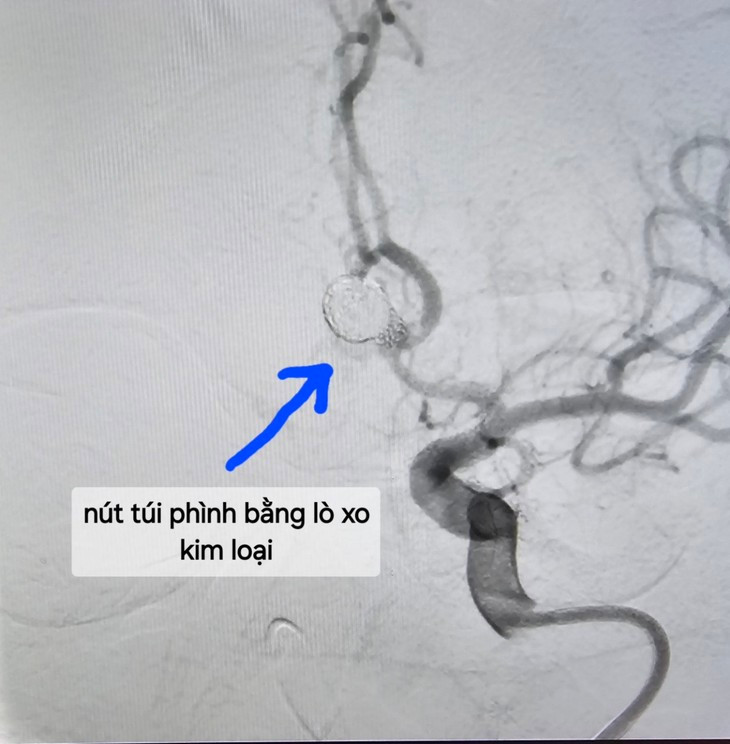

Nút túi phình bằng lò xo kim loại - Ảnh BVCC

- Nút túi phình mạch não: có thể can thiệp nút bằng sợi kim loại, hoặc phẫu thuật túi phình…